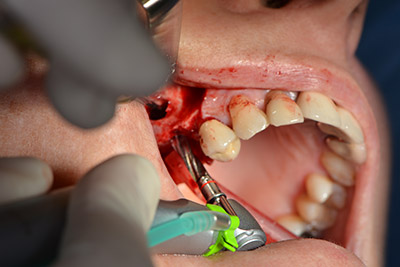

El guiado clásico del corte (crestal, descarga bucal) y la preparación del colgajo mucoperióstico permiten obtener una buena visión global.

En este caso se utilizan implantes Sky (Bredent), cuyo protocolo quirúrgico exige el fresado piloto a unas 1.200 rpm (figura 9).

Las perforaciones siguientes se realizan a una velocidad reducida de 300 rpm. Y es aquí donde se demuestra una de las ventajas de Implantmed. El protocolo quirúrgico puede predefinirse y las diferentes posiciones pueden seleccionarse pisando el pedal hacia la posición "P" (figuras 10 a 11).